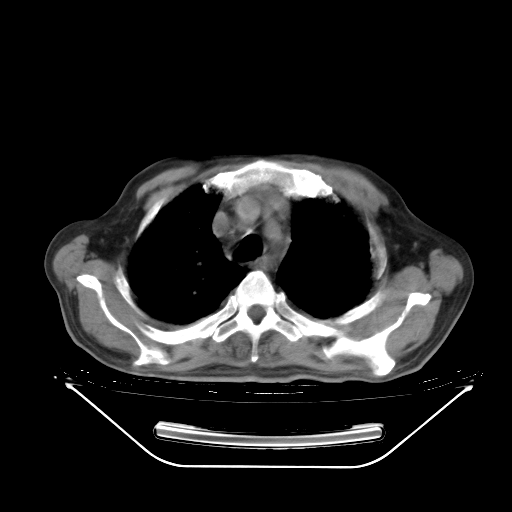

今天复查肺部CT,发现双肺广泛磨玻璃样改变。所以我把3月19日和5月9日相隔50天的肺部CT上传。请大家会诊。

2009年3月19日肺部CT片。

2009年3月19日肺部CT

大致读了系列胸部CT:纵隔窗无明显异常,肺窗:从4、27至今:主要是双肺中下野外带可见毛玻璃样改变,目前处于急性肺泡炎阶段,至于原因考虑1、结替组织或胶原血管性疾病所致?2、恶性疾病如恶组在肺部所致的表现或细支气管肺泡癌?3、药物或其它原因如肺蛋白沉着症所致肺泡炎目前不太可能?总之,明天就去请我院的呼吸科、感染科、血液科和临免专家会诊哈。